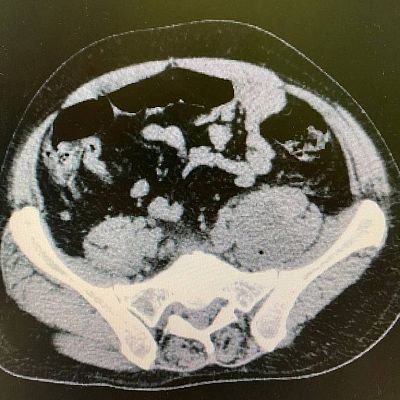

При дообследовании в стационаре выявлены высокие показатели маркеров воспаления, указывающие на септическое состояние пациента, плюс усиливающиеся боли… Дальнейшее обследование мужчина уже проходил в реанимации. По результатам компьютерной томографии у него выявлен ранее перенесенный перелом суставных отростков 4-го поясничного позвонка и абсцесс в структуре правой поясничной мышцы - источник сепсиса установлен. Именно этот абсцесс доставлял пациенту столько страданий и даже мешал лежать на спине.

«Вскрытие гнойных полостей в этой анатомической области представляет значительные трудности для хирурга и большой травматизм операции для пациента, - говорит проводивший операцию заведующий отделением экстренной хирургии Артем Александрович Косов. - В виду чего было принято решение о попытке минимально инвазивного вмешательства, избежав полостной операции с неизбежным рассечением мышечной ткани. Мы нашли небольшое ультразвуковое окно, позволяющее произвести дренирование указанного абсцесса, через переднюю брюшную стенку, при этом не затрагивая брюшную полость».

Ювелирно, под местной анестезией и в миллиметровой близости от магистральных сосудов (подвздошные артерия и вена проходили в 3 мм от места пункции) и сигмовидной кишки (расстояние до нее составляло 5 мм), наши врачи под УЗИ-контролем выполнили пункционное дренирование полости абсцесса, эвакуировав 400 мл гноя!